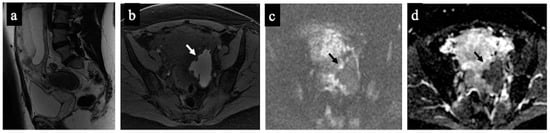

Figure 1. Decidualised endometrioma. MR images of a 37-year-old woman—16 weeks pregnant—with an indeterminate adnexal lesion discovered at the first-trimester US. The sagittal (a), axial T1-WI with fat-saturation (b), DWI (c) and ADC map (d) show a unilocular cystic left adnexal mass with haemorrhagic content (high signal intensity on the T1-WI with fat saturation) and some small papillary projections (arrows). Note how the small papillary projections have an intermediate signal on the T2-WI but no corresponding true diffusion restriction (high signal in both DWIs on ADC-map), so they are not considered “solid tissue” according to the NCMS. The lesion was considered indeterminate according to the SA by the non-expert radiologist, who correctly reclassified it as a score of 2 using the NCMS (false positive/true negative).